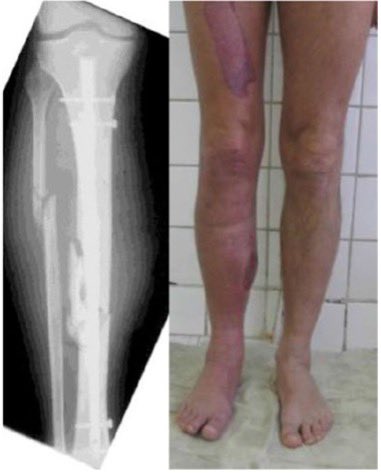

- تركيب مسمار النخاع (Intramedullary nail): يتم إدخال قضيب معدني مصمم خصيصًا في قناة الساق و يمر القضيب عبر الكسر لإبقائه في موضعه مما يساعد على التئام الساق.

- التثبيت الخارجي (External fixation): عبارة عن إطار خارج الساق يتم تثبيته في العظام بدبابيس، يوفر هذا الجهاز الثبات للعظام خلال فترة الالتئام و تتم إزالته عادة بعد التئام الكسر.